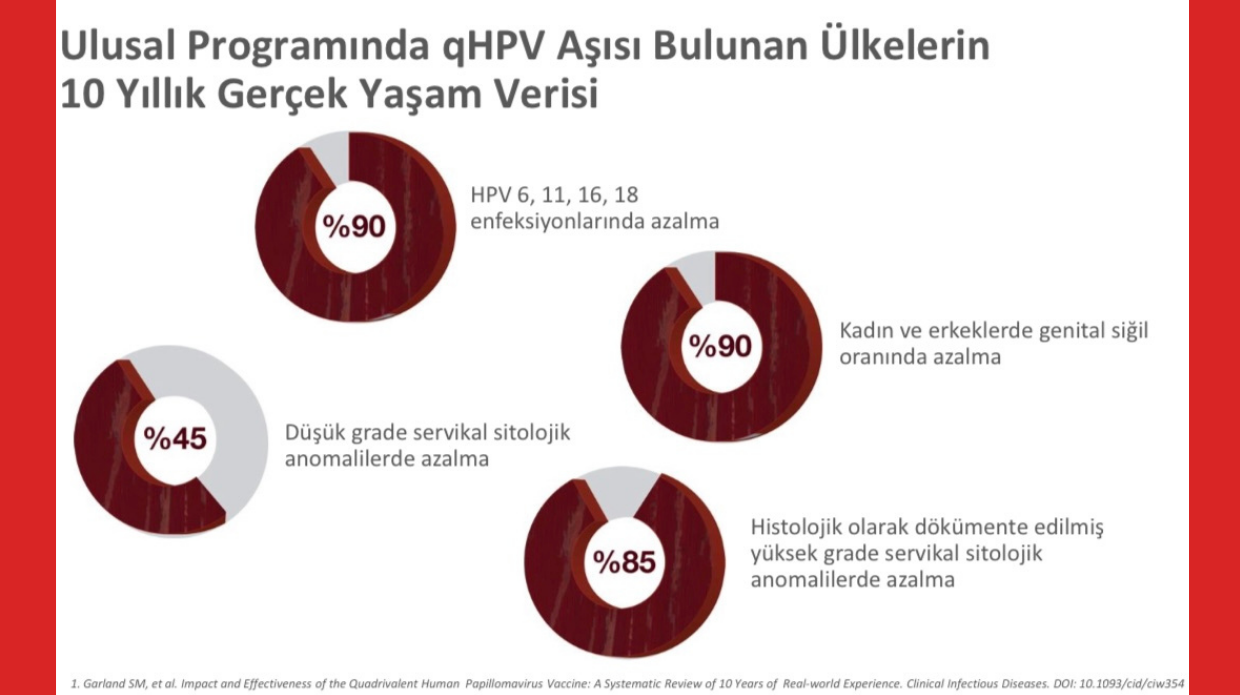

Çünkü şu bilgilere de sahibiz: 10 yıl boyunca ulusal aşı takviminde çocuklarını aşılamış bir ülkenin gerçek yaşam verisine göre HPV enfeksiyonlarında ve genital siğillerde %90 azalma, yüksek dereceli kanser öncüsü lezyonda (CIN2-CIN3) yüzde %85 azalma sağlandığı görüldü. İnsanlık tarihinde 10 yıl çok kısa bir süre ve bu etki çok iyi bir oran.